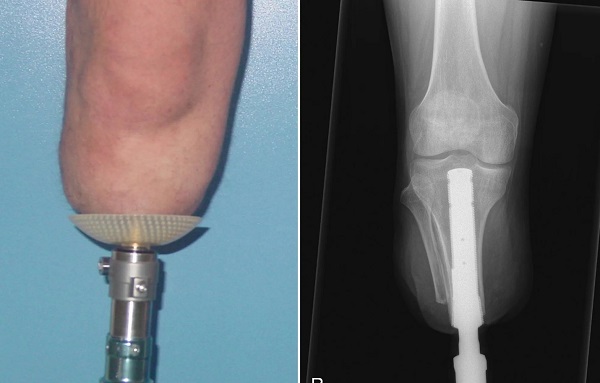

پروتز اسئواینگریشن (Osseointegration)

این پروتز برخلاف دیگر پروتزها، شامل جراحی و کاشت ایمپلنت فلزی درون استخوان میشود. این ایمپلنت کاشته شده پس از بهبود، طی فرایندی به نام اسئواینتگریشن با استخوان پیوند خورده و امکان اتصال محکم را با پروتز برقرار میکند. این پروتز امکان تحرک بیشتر و عملکرد بهتری را برای استفاده کننده فراهم میآورد. افرادی که توانایی استفاده از سایر پروتزهای سوکت دار را ندارند، گزینه مناسبی برای استفاده از پروتز اسئواینتگریشن هستند.